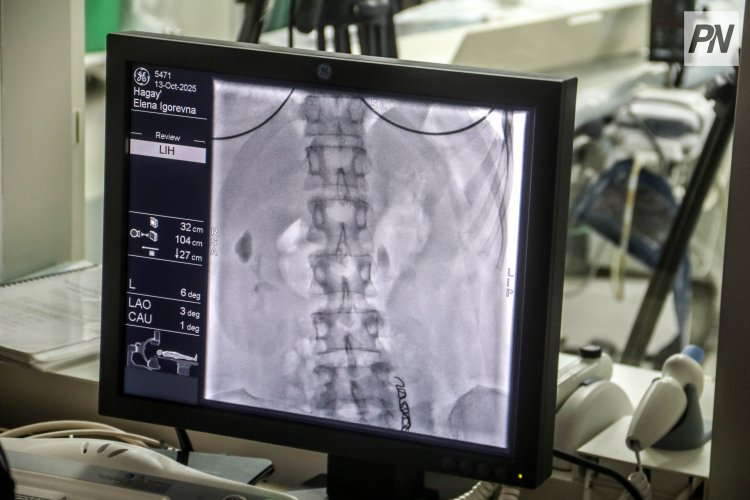

– Варикозно расширенные вены часто бывают у женщин, у которых было много беременностей и родов. Мы приехали в Павлодар помочь таким пациенткам, – сообщил врач. – Через маленький прокол на руке проводится тонкий катетер в кубитальную вену, куда имплантируется специальная спираль, перекрывающая патологический кровоток. Процедура называется эмболизацией.

По его словам, операция выполняется под местной анестезией, без наркоза и без разрезов. Пациент в сознании, находится на контакте с хирургами. В венах нет нервных окончаний, поэтому человек не чувствует манипуляции.